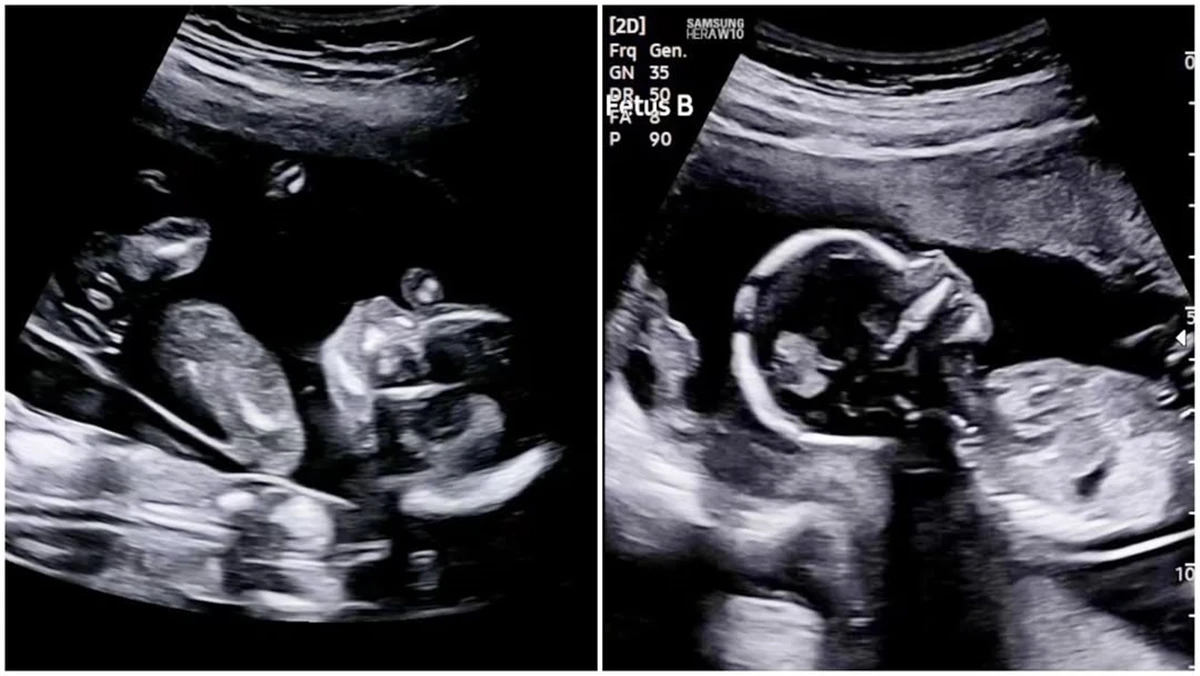

도광록은 "안녕하세요 도광록입니다. 여러분 저... 쌍둥이 아빠 됩니다! 심지어 아들, 딸이래요. 태명은 꿈이, 감동이. 내일이면 벌써 21주입니다"라며 쌍둥이의 아빠가 됐다는 소식과 함께 초음파 사진을 게시했다.

도광록은 "처음 임신 소식을 들었을 때는 기쁘기보다 어안이 벙벙하고 걱정이 더 컸습니다. 그런데 시간이 지날수록 사랑하는 와이프 배는 점점 불러오고 초음파 속에서 작게 움직이는 모습을 보니까 이제야 조금씩 와닿습니다"라며 쌍둥이 아빠가 된 소감을 전했다.